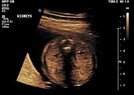

New Born baby with single kidney (Renal agenesis)

New Born baby with one kidney.

What will be the line of treatment for this rare birth defect (disorder)?

• images - 2022-03-16T105439.419.jpeg

images - 2022-03-16T105439.419.jpeg

10.3 KB · Views: 194